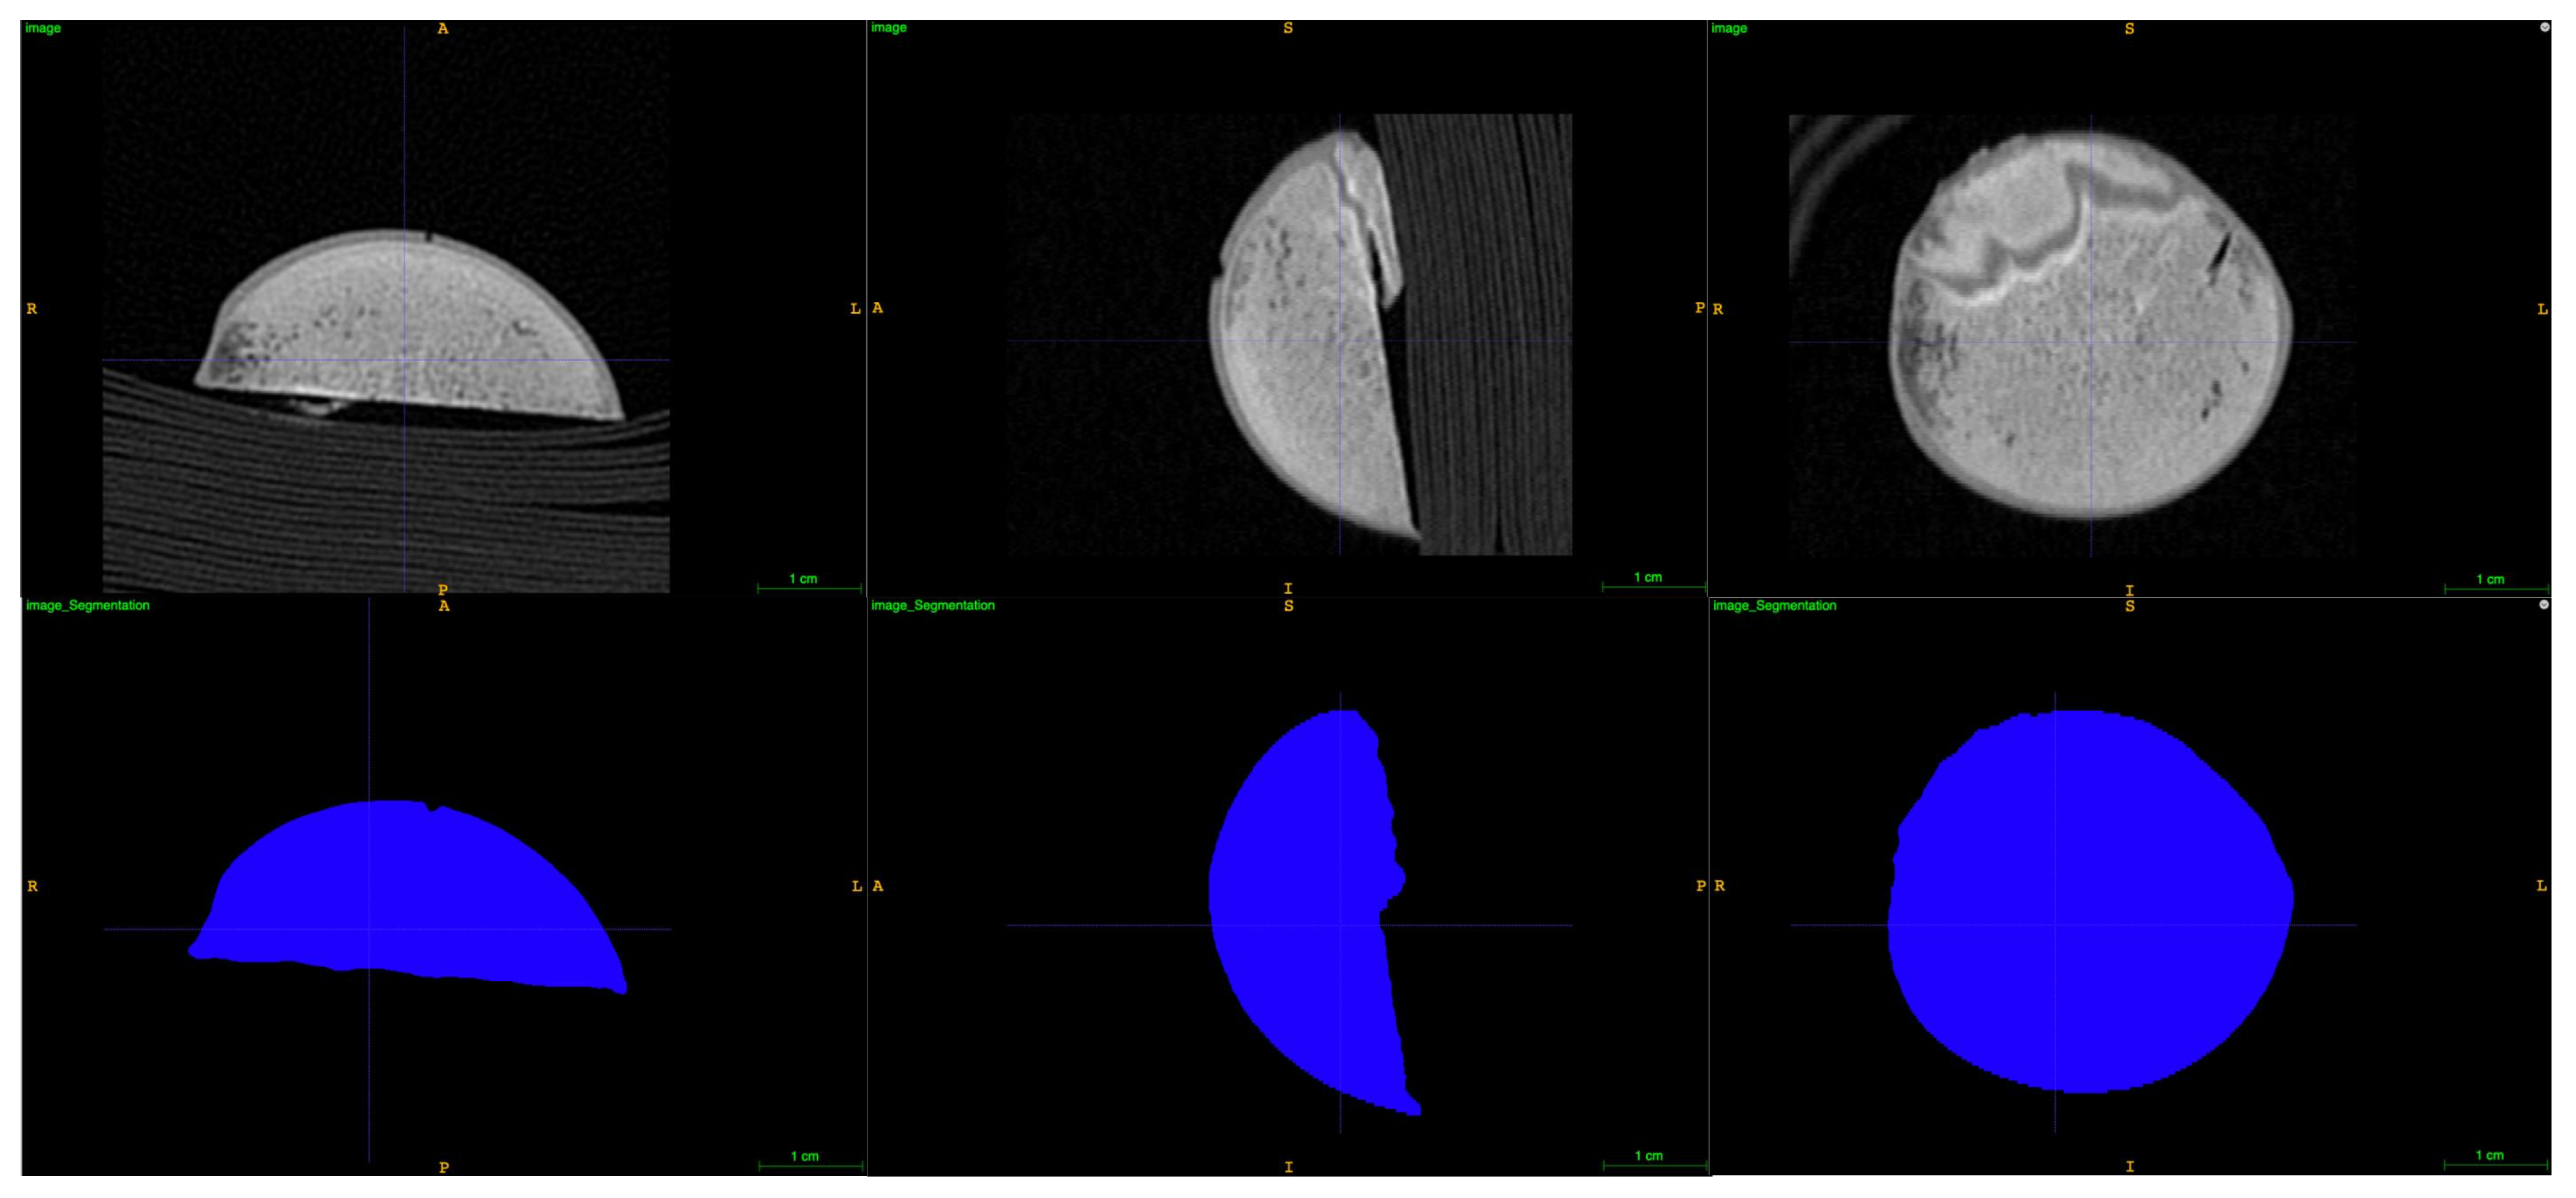

| Comparison of Weight groups | Group 1 53–57 kg | Group 2 73–77 kg | Group 3 93–97 kg |

|---|---|---|---|

| Humeral head size: Volume, mm3 (95% CI) | 14,413 (10,941–17,885) | 17,971 (14,499–21,443) | 22,361 (18,889–25,833) |

| Deadspace fT > MIC, min (95% CI): First dosing interval | 333 (241–424) | 255 (163–346) | 245 (148–341) |

| Deadspace fT > MIC, min (95% CI): Second dosing interval | 321 (230–412) | 378 (287–469) | 315 (219–412) |

| AUCdeadspace/AUCplasma (95% CI): First dosing interval | 1.87 (1.38–2.35) | 1.77 (1.29–2.25) | 1.27 (0.79–1.76) |

| AUCdeadspace/AUCplasma (95% CI): Second dosing interval | 1.13 (0.65–1.61) | 1.70 (1.22–2.19) | 1.19 (0.68–1.71) |